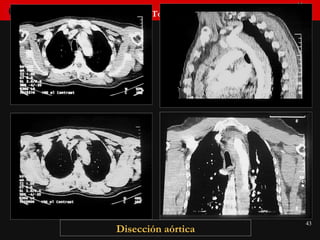

DISECCION AORTA  TORACICA Derrame pleural Derrame pericárdico Consolidación parénquima Cambios evolutivos  Tórax normal Otros signos de disección

Disección aórtica